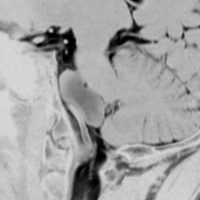

5歳の時に発見され23歳まで18年間経過観察をされてきた患者さんです。腫瘍はゆっくり,しかし確実に増大して,手術前には頭痛がひどく薬も効かず歩けなくなったという症状でした。術後に頭痛が無くなったので,のう胞による症状だったのでしょう。

下垂体柄の周囲にのう胞性腫瘍があります。T1強調画像では等信号,T2強調画像ではまだらな信号になっています。23年という長い経過から液状内容物が固形化したものと推定されます。T2で低信号となる部分があるのですが,黄色肉芽腫とは異なる像です。

下垂体柄は長く伸びています。のう胞による長期の圧迫のため斜台上部がerosionになって凹んでいます。トルコ鞍内の中間葉の位置に典型的な小さなラトケのう胞(黄色矢印)がみられますが,これは長年変化していませんでした。

左前頭側頭開頭 pterional approachで,のう胞壁を含めて完全摘出 complete removalしました。のう胞は下垂体柄の左側に付着してそこから発生したものでした。内容物は固体で寒天状のコロイドでした,一部軟らかくて一部は線維化していました。のう胞壁は半透明で薄い部分も線維性の膜状の部分もありました。病理検査では上皮細胞が証明されて内胚葉のう胞 endodermal cystの診断です。

ラトケのう胞はhiatusから内容液吸引だけして,皮膜はもちろんそのままにしています。